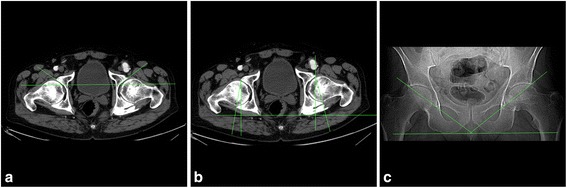

Next, a comparison between our method and classic 2D measurement was made to authenticate the new technique. Thirty adult pelvic CT scans (28 males, 2 females; 60 acetabula) were included in the study. Records were taken consecutively from patients with surgical, non-orthopedic diagnoses who were free of any pelvic bone lesions. The 30 CT scans were assessed using the following 2D angles: anterior acetabular index (AAI) (Figure 6a) and acetabular anteversion angle (AAA) (Figure 6b) in the horizontal plane [32]; and abduction angle in the frontal plane (based on the topogram taken at the beginning of the CT-scanning process) (Figure 6c) [33], the angle between the line connecting upper lateral and lower medial rims of the acetabulum and the line connecting the lower edge of the ischial tuberosities. Abduction angle was measured in 25 cases, as topograms were not recorded for three male and two female patients. A 3D model of the pelvis was then generated based on the scans previously obtained, and all measurements were performed.

Figure 6.

Angles measured using two-dimensional technique: (a) Anterior acetabular index, (b) acetabular anteversion angle, and (c) abduction angle based on the topogram.